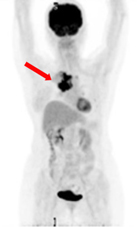

正常氟-18去氧葡萄糖於體內生理分佈

腫瘤細胞明顯增加代謝 (箭頭處)